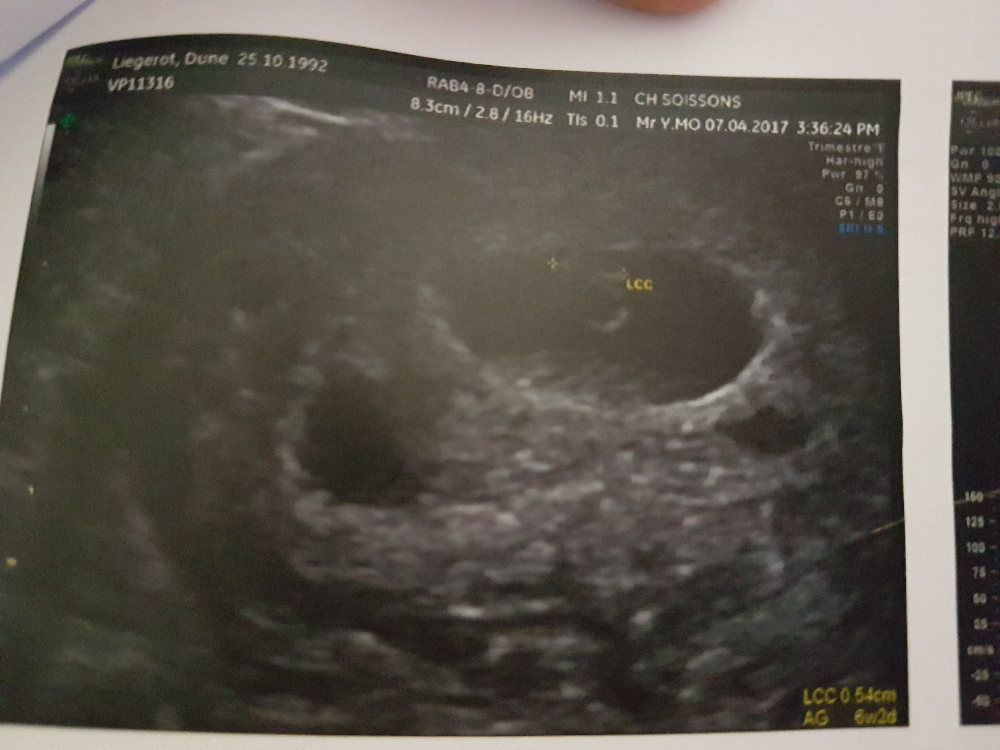

Bebe a 6 semaine de grossesse echographie-J'ai rendez vous pour ma 1ère échographie à 6 semaines de grossesse , on va entendre le coeur du bébé ?Bien entendu, c'est aussi parce que bébé a besoin de tout ce temps pour mettre de l'ordre dans son nouvel abri À 6 semaines de grossesse (8 semaines d'aménorrhée), bébé est de la taille d'une graine de pavot L'embryon moyen à la sixième semaine mesure environ 15 mm (pour au plus 3 grammes de poids), cette taille devant

Je suis à 23eme semaine de grossesse, j'ai effectué une échographie il y a deux jours, et je veut savoir si vous permettez si les valeur de BIP DAT et LF sont normales BIP 557 DAT533 LF434 merci Aucune interprétation de résultats d'analyse ne peut être faite sur le forum Cette question est à poser à ton médecin Si votre médecin ne vous le propose pas, vous pouvez demander une radio du bassin, aussi appelée pelvimétrie elle est généralement réalisée au dernier trimestre de grossesse, autour des 37 semaines Cela permettre de voir si votre bassin n'est pas trop étroit Néanmoins, là aussi il y s'agit d'une estimation De plus, leéchographie a 6 semaines de grossesse Résolu /Fermé juste un renseignement, je voudrais savoir pour celle qui on aussi fait une échographie à 6 semaines ce que vous avez vu exactement, moi j'ai vu le petit bebe dans le sac et le tache blanche qui clignote qui est le coeur qui bat, le mec qui m'a fait l'échographie m'a dit que j'etais enceinte de 6 semaines car je ne savais pas de quand remontait la grossesse mais il ma dit qu'il voulais me revoir a 8 semaines car le coeur du bebe

A 5 semaines de grossesse, notre maman a fait une échographie précoce L'embryon était là mais elle n'a entendu aucun battement de coeur, et elle se demande si c'est normal La réponse deEst ce qu'on voit bien pour la 1ère échographie ?Cette première échographie peut être réalisée dès la 6 ème semaine de grossesse À ce stade de la grossesse, on peut déjà apprécier la présence de l'embryon et surtout l'existence d'un battement cardiaque, celui du futur bébé

Premières semaines de grossesse Sans aucun doute, le premier indice qui vous permettra de découvrir que vous êtes enceinte est l'absence de règles L'activité cardiaque du fœtus est visible aux alentours de 6 a 7 semaines de grossesse Parfois, à un jour près, elle peut encore être absente, d'où l 'importance de savoir attendre et de ne Echographie de datation comment ça se passe ?

La semaine 10 de Grossesse Cette 10e semaine de grossesse est marquée par votre première échographie, la première rencontre avec ce petit être qui se développe en vous Normalement, les nausées se calment et c'est sereinement que vous pourrez voir votre bébé pour la première foisLe cœur de votre bébé commence habituellement à battre vers la 6 e semaine de grossesse Si vous n'entendez pas ou ne voyez pas de battement de coeur à 6 semaines lors d'une échographie, il est tout à fait naturel que vous soyez inquiet Les médecins pratiquent généralement 3 échographies pendant la grossesse Elle permet d'avoir des informations sur le fœtus et de suivre son évolution La première se fait autour de la 12e semaine, la seconde vers la 22e semaine et la dernière à la 32e semaine – L'échographie de la 12e semaine (soit entre votre 12e et 14e